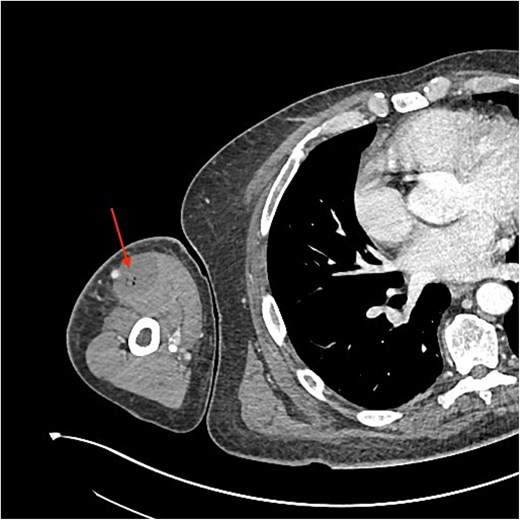

An urgent review by the plastic surgery team prompted a bedside sweep test to assess for necrotizing fasciitis. The dermis, fat and fascia did not show any evidence of venous thrombosis or typical ‘dishwater fluid’, synonymous with typical necrotizing fasciitis (Fig. 2). This is a negative test for necrotizing fasciitis (negative predictive value = 100%) [3]. With no clear cause of the sepsis and progressive limb swelling, a CT scan of the arm was requested. The report described a fluid collection containing gas locules within the biceps (Fig. 3).

In our patient, the initial CT report described a fluid collection within the biceps muscle with gas locules, suspicious of necrotizing fasciitis. This guided the immediate surgical management and hence debridement of the infected muscle. However, because the source of infection was not adequately controlled, the patient continued to deteriorate. Only when the CT was re-reported by an MSK radiologist that collections deep to the deltoid and involving infraspinatus and subscapularis were noted and could subsequently debrided. This highlights the clinical and radiological diagnostic challenges with this case.